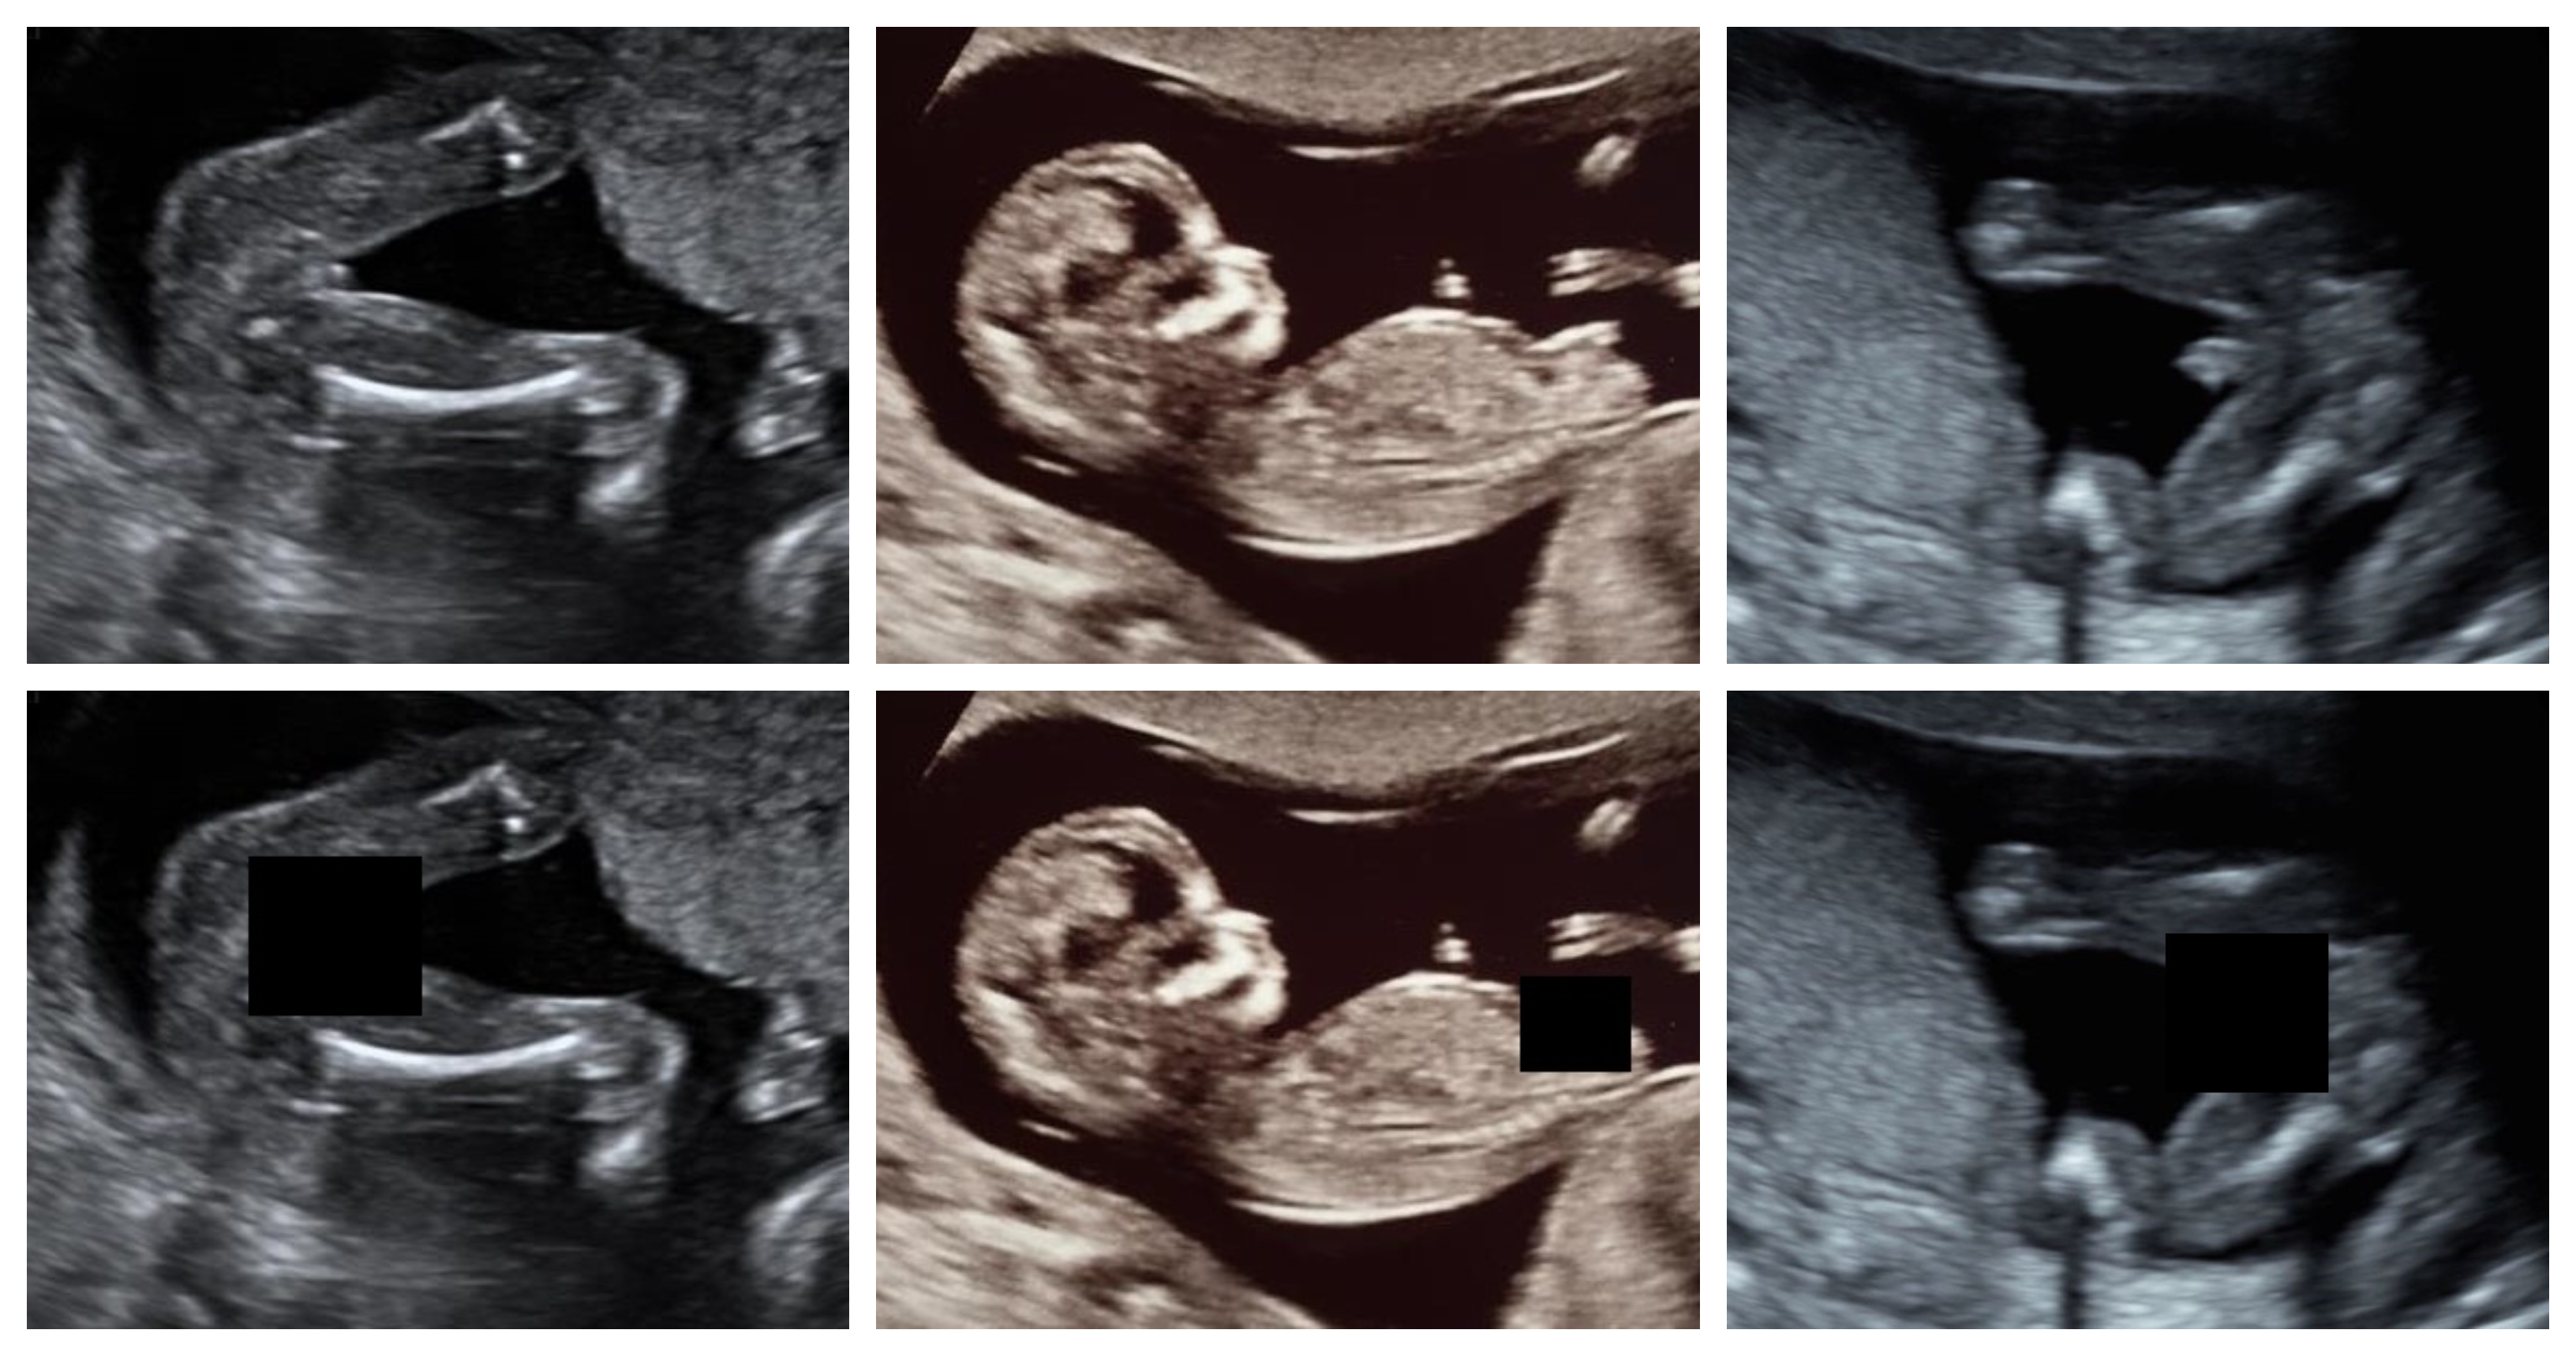

Fig. 1 depicts a few sample annotations.

The results of the YOLOv5L and EfficientDet-D3 (AdvProp) models show a very high performance of over 90% label F1-score, with the YOLOv5L model’s higher demonstrating a better average precision over different IoU thresholds. Fig. 2 depicts sample detection and masking on images from the test set using YOLOv5L. In order to further analyze the performance of the best performing YOLOv5L model, further investigation into False Positives and False Negatives will be made in the following sections.